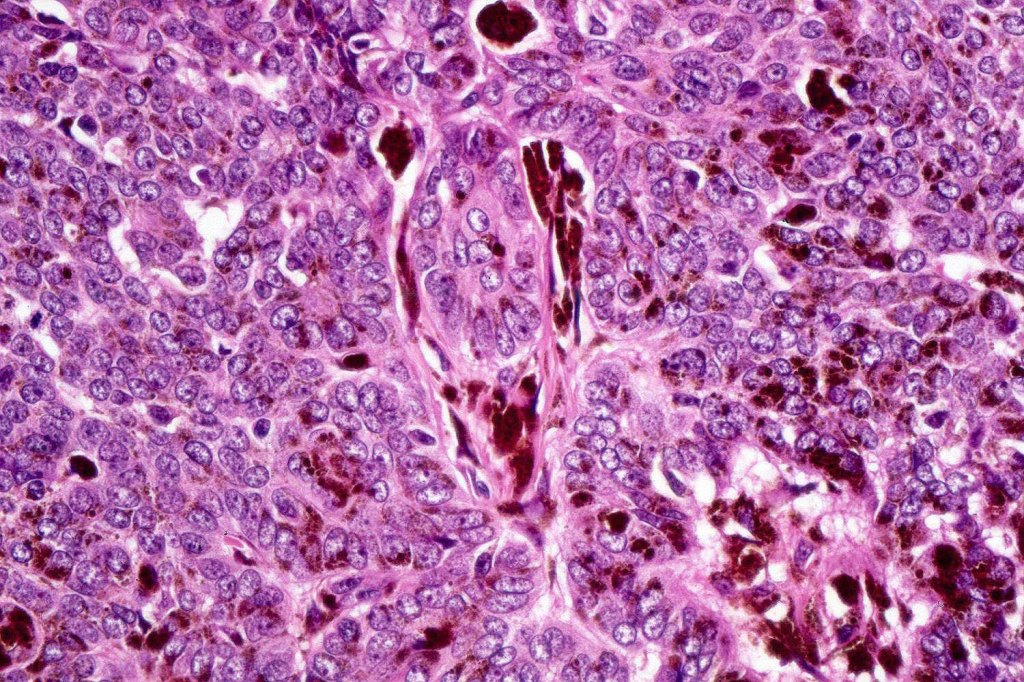

•Variably sized but generally large, basophilic tumor nodules composed of small uniform basaloid cells with minimal cytoplasm

•Variable mitotic activity, can be brisk

•No pleomorphism or abnormal mitoses

•Peripheral palisading but no retraction artifact or stromal mucin deposition